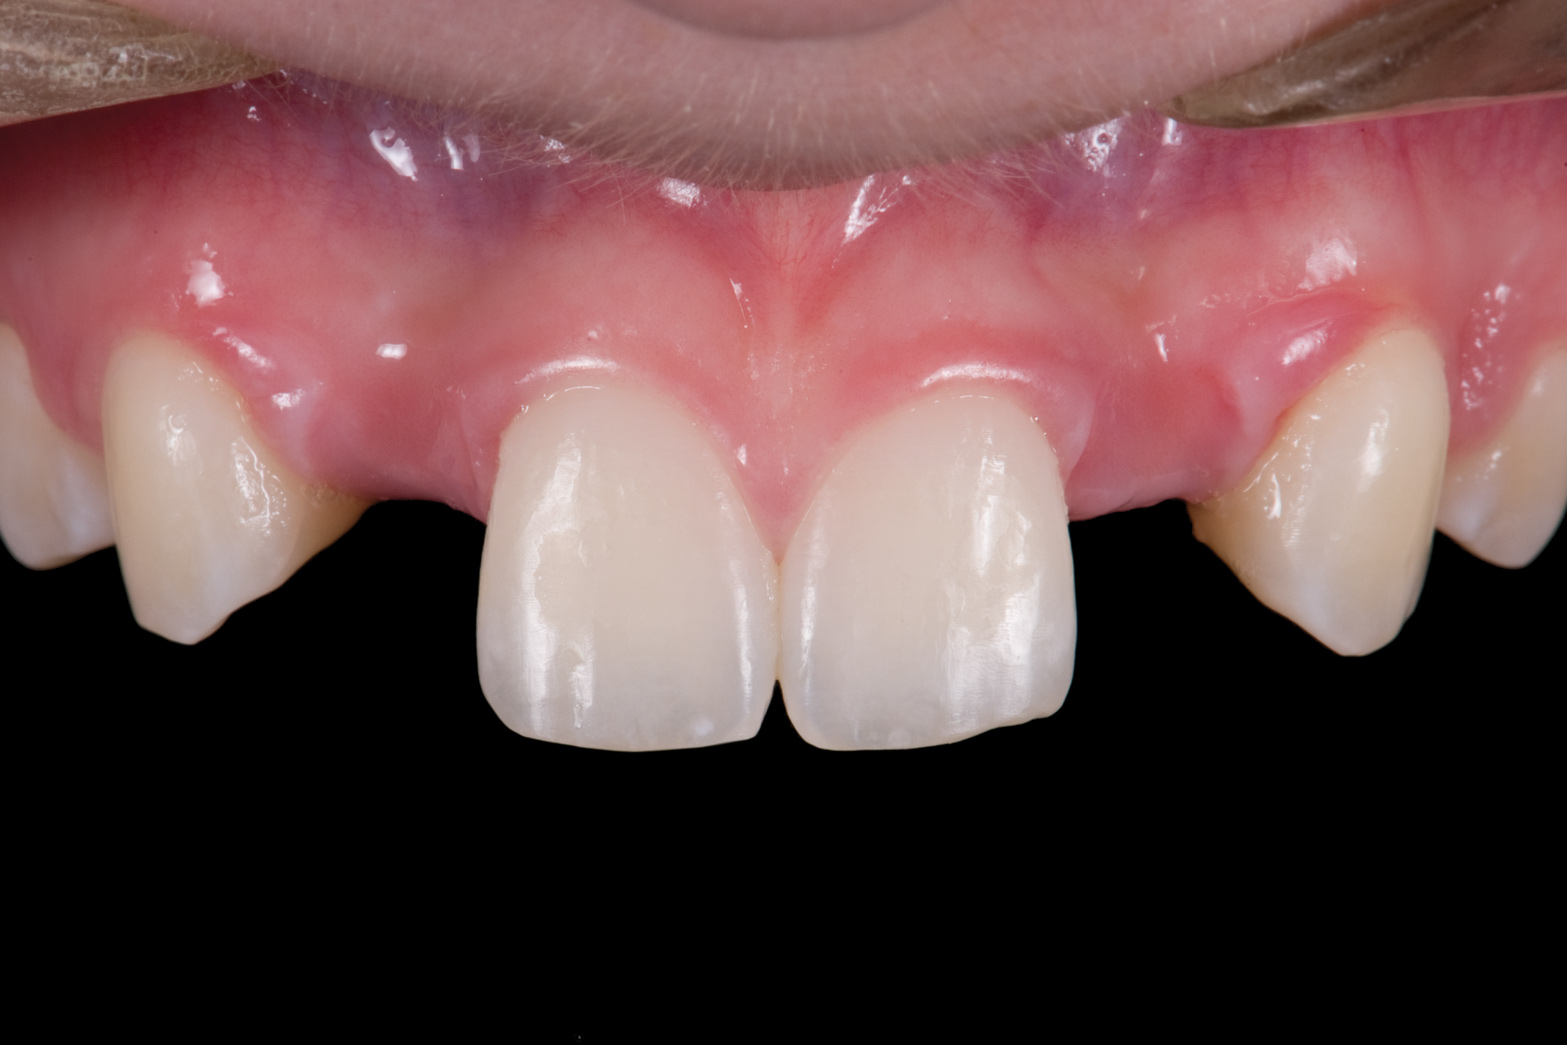

Fig 12. 15-year-old girl after orthodontic therapy idealized maxillary lateral incisor spaces.

Figure 12

Fig 13. Deficient ridges in the areas of the missing lateral incisors.

Figure 13